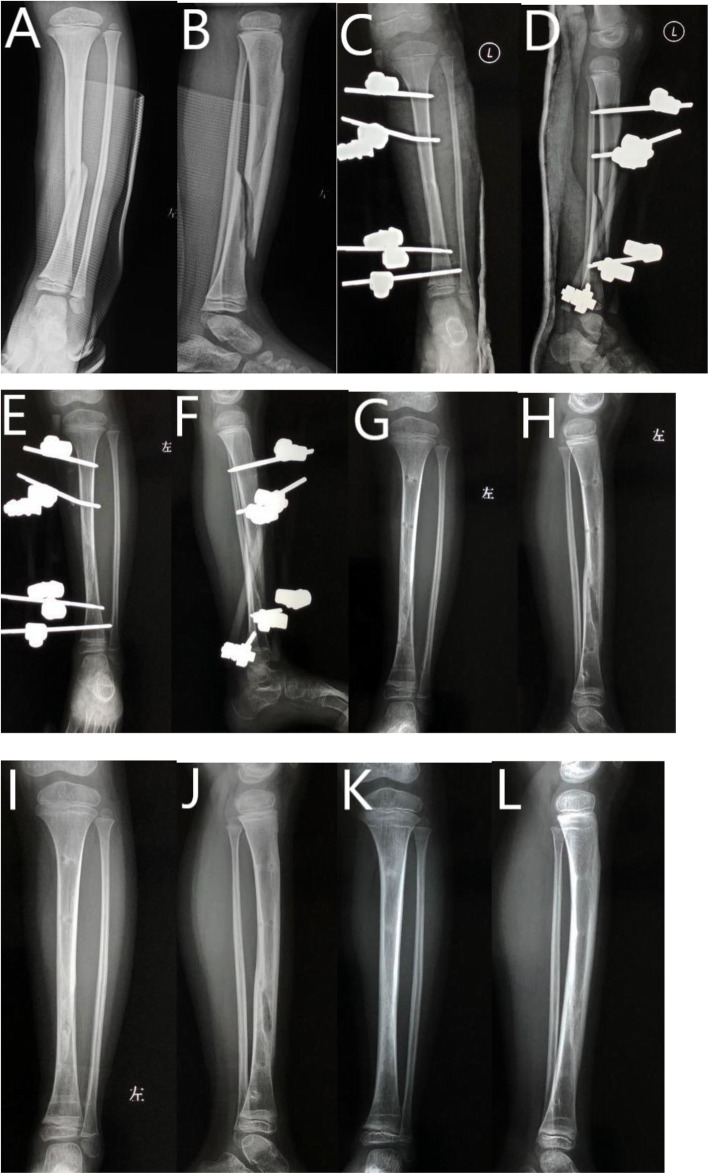

Fig. 1.

Six-year-old boy with Gustilo-Anderson grade II tibial fracture treated with EF. A AP view of tibia before surgery. B Lateral view of tibia before surgery. C AP view of tibia after surgery. D Lateral view of tibia after surgery. E AP view of tibia at 8th week follow-up. F Lateral view of tibial at 8th week follow-up. G AP view of tibia after hardware removal at 11th week follow-up. H Lateral view of tibia after hardware removal at 11th week follow-up. I AP view of tibia at 5th month follow-up. J Lateral view of tibia at 5th month follow-up. K AP view of tibia at 12th month follow-up. L Lateral view of tibia at 12th month follow-up